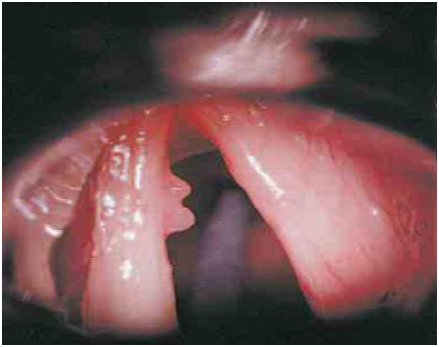

Il est le plus souvent très facile : une simple laryngoscopie indirecte au miroir laryngé ou au fibroscope suffit, en général, à affirmer une paralysie récurrentielle sur la constatation de l’immobilité d’une des deux cordes, tant en phonation qu’en inspiration. La position de la corde paralysée est variable.

– Elle peut être fixée en position médiane, c’est-à-dire en adduction.

– Exceptionnellement, elle est en abduction complète.

– Le plus souvent, la corde paralysée est immobilisée en position intermédiaire, c’est-à-dire en semi-abduction.

Lorsque la dysphonie est ancienne, on peut observer des modifications anatomiques du larynx : bascule antérieure de l’aryténoïde du côté paralysé, atrophie et abaissement de la corde atteinte. De même peut-on observer des phénomènes de compensation : en phonation, la corde saine tend à dépasser la ligne médiane pour tenter de s’affronter à la corde paralysée en position paramédiane.

L’importance de la dysphonie est liée à l’importance de la fuite glottique en phonation, donc à la position de la corde paralysée et aux possibilités de compensation par la corde opposée.